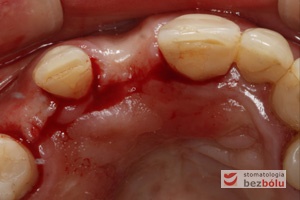

Pierwszy etap zabiegu implantologicznego - kształt cięcia błony śluzowej - przesunięty do podniebienia - zapewniający dostęp do kości

Pierwszy etap zabiegu implantologicznego – kształt cięcia błony śluzowej – przesunięty do podniebienia – zapewniający dostęp do kości